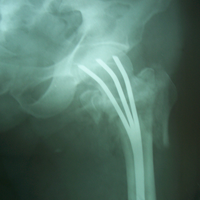

Case:7 Fracture Neck Femur with Implant failure and Re-Fixation with hemi-arthroplasty

Alcoholic Gardener by profession had slipped in bathroom & fell. He sustained fracture neck femur.He was operated with closed reduction & CC Screw fixation under IITV. Two weeks’ post fixation he again fell & sustained fracture in sub trochanteric region. He was treated with Hem-Arthroplasty with Tension band wiring.

Pre-Op